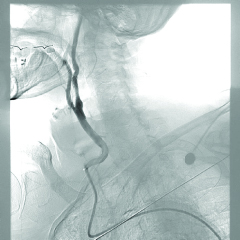

The team proceeded with ultrasound-guided right common femoral artery access. The patient had a Type 3 aortic arch, which made advancement of the catheter difficult due to a sharp angle (Figure 3). Therefore, a curved sheath technique was used with 6-Fr vascular sheath. The Cook 90 cm Shuttle Sheath was manually curved by the operator and then positioned in the right common carotid artery. This was followed by crossing the stenosis using a 0.014 Whisper wire. Eventually, a Medtronic Protege 8–6 × 40 mm carotid self-expanding stent was placed at the site of the lesion in the internal carotid artery after placing the SpiderFX embolic protection device, since other filters were unpassable, which significantly reduced the risk of emboli (Figure 4). After the procedure, the patient was transferred to the CICU in stable hemodynamic condition. Post-operatively, he developed bradycardia without hypotension transiently requiring chronotropic support with a dopamine infusion, from which he was successfully weaned off in a day. Reflexive bradycardia is a well described post-procedural phenomenon following internal carotid artery stenting.

Figure 3

Figure 3. Type III Aortic Arch. Angiogram shows that the patient has Type III aortic arch ≥2 diameter of common carotid artery.